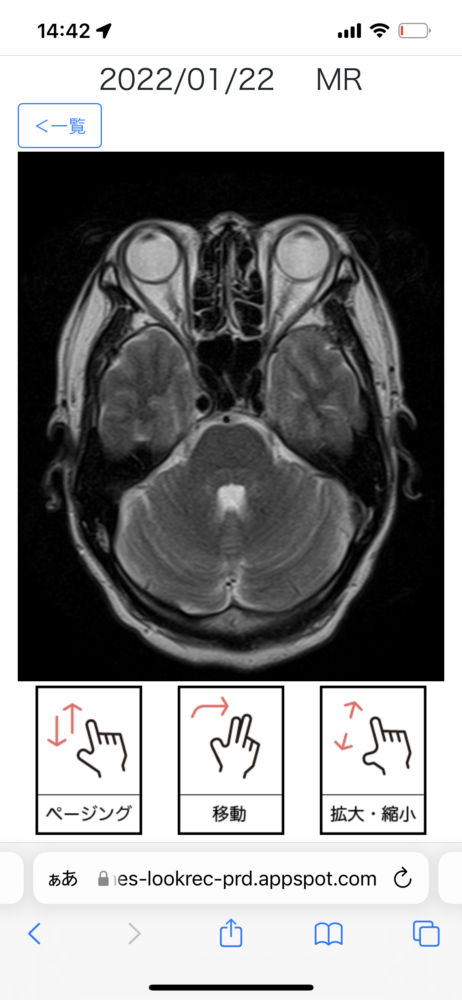

これは脳血管のMRI画像だそうだが、スクロールすることでグルグル回しながら立体形状を見ることができる。これにより静脈瘤などを見つけ出すことができるのだそうだ。

目玉の奥の視神経はこうなっているのか……鼻の穴の中の空洞はこうなっているのか……と、自分のスライスされた画像を見るのは興味深い。